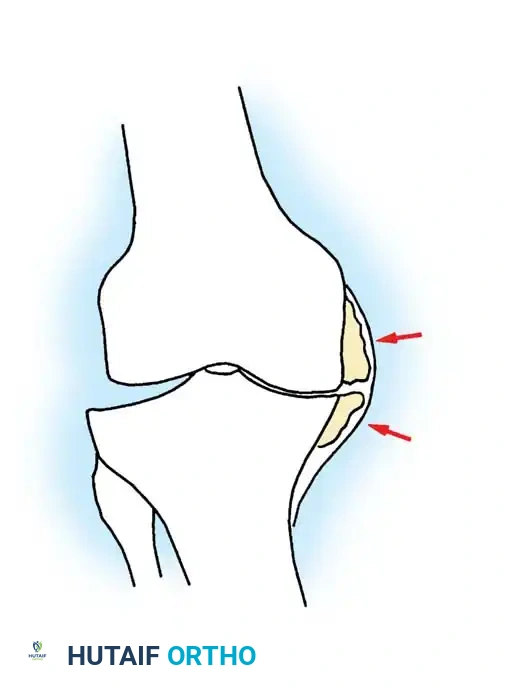

- Remove any prominent osteophytes (especially in the intercondylar notch and medial/lateral gutters) that may lead to component malposition, impinge on soft tissues, or create artificial soft-tissue tension.

- Expose the lateral tibial plateau by partially excising the infrapatellar fat pad and carefully placing a levering-type retractor adjacent to the lateral tibial plateau.